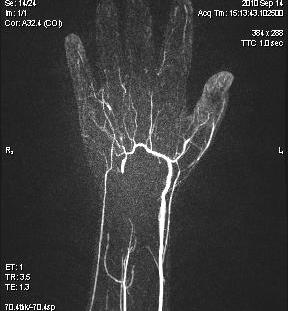

Scleroderma

Pathophysiology

Autoimmune disease

Unknown aetiology

Small vessel disease

Fibrosis in multiple organ systems

X-ray

1. Calcium subcutaneous / extra - articular / occasionally intra-articular

2. Acro-osteolysis of the tufts of DP (80% patients)

Osteopenia

Joint erosion

- RA part of DDx

Resorption of thumb CMC

- subsequent radial subluxation of the thumb MC